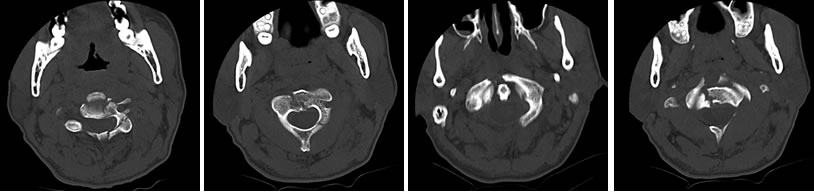

4月24日晚,48岁的王先生因外伤致头颈部疼痛1个多小时,于23点收入我院闽南医院神经外科。经检查,其被诊断为:1.右额、颞部硬膜外血肿;2.右额骨、右颞骨、右蝶骨骨折、右颧骨骨折;3.颈1、2、3骨折脱位,寰椎后弓大部先天缺失。在医护人员的积极治疗下,病人颅脑出血得到控制,于4月25日转入骨科继续治疗。

针对王先生的病情,骨科主任陈飞博士组织全科进行大讨论,认为病人系高位颈椎多发损伤,合并先天性寰椎后弓大部缺失畸形、寰枢椎半脱位,随时有全身瘫痪和死亡的危险,这类病人在省属三甲医院都并非常见。精心讨论后,治疗组决定先行颅骨牵引,进行颈椎复位,待全身情况稳定后行高位颈椎内固定融合术。

上颈椎的解剖结构非常复杂,周围有众多的主要神经、血管,手术操作时稍有不慎,就可能招致灾难性的后果,加上患者寰椎后弓的发育不全,造成延髓处骨性屏障缺失,以及显露、置钉时的解剖标志丧失,极大地增加了手术的难度以及风险。为保障安全,医院根据患者高精度CT三维扫描的原始数据,依托院外高新科技3D打印实验室,制作出1:1的上颈椎模型,真实还原了患者上颈椎骨折及畸形的情况。根据3D打印模型,骨科团队在陈飞博士的主持下进行多次的模拟手术,在毫米级别上,精确地定位了内固定物的置入点、明确了螺钉的方向、直径和长度,并对手术中可能出现的意外作了充分的估计和预演。